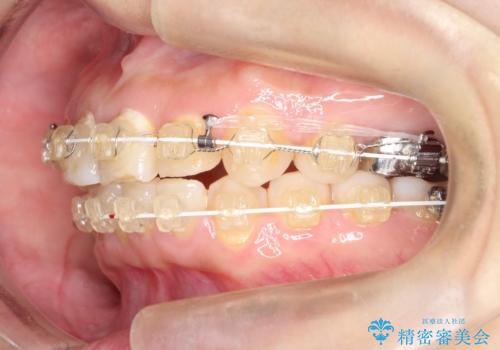

【ワイヤー矯正】前歯が出てるのをなおしたい。

- 矯正装置

- 審美装置

- 2年9ヶ月

- 前歯の凸凹を主訴に来院されました。